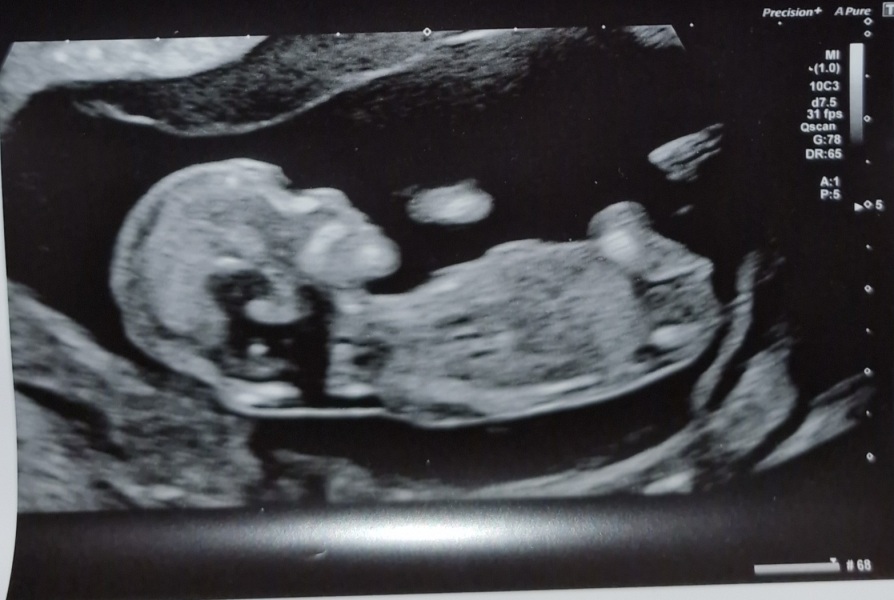

12 week scan gender guess

Hi all, had 12 week scan. Could anyone guess gender based on pic?

Fun guess girl 🩷